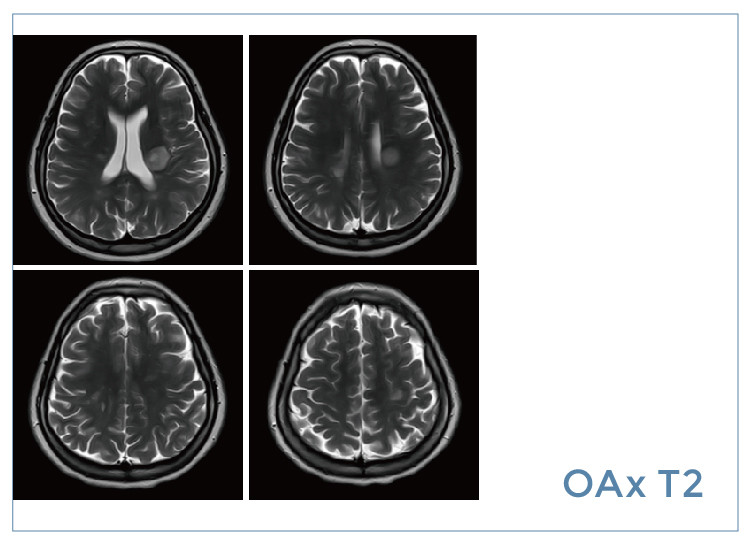

【朗润影像档案】20190823磁共振影像病例结果讨论

【朗润影像档案】磁共振影像病例分享(编号20190823)